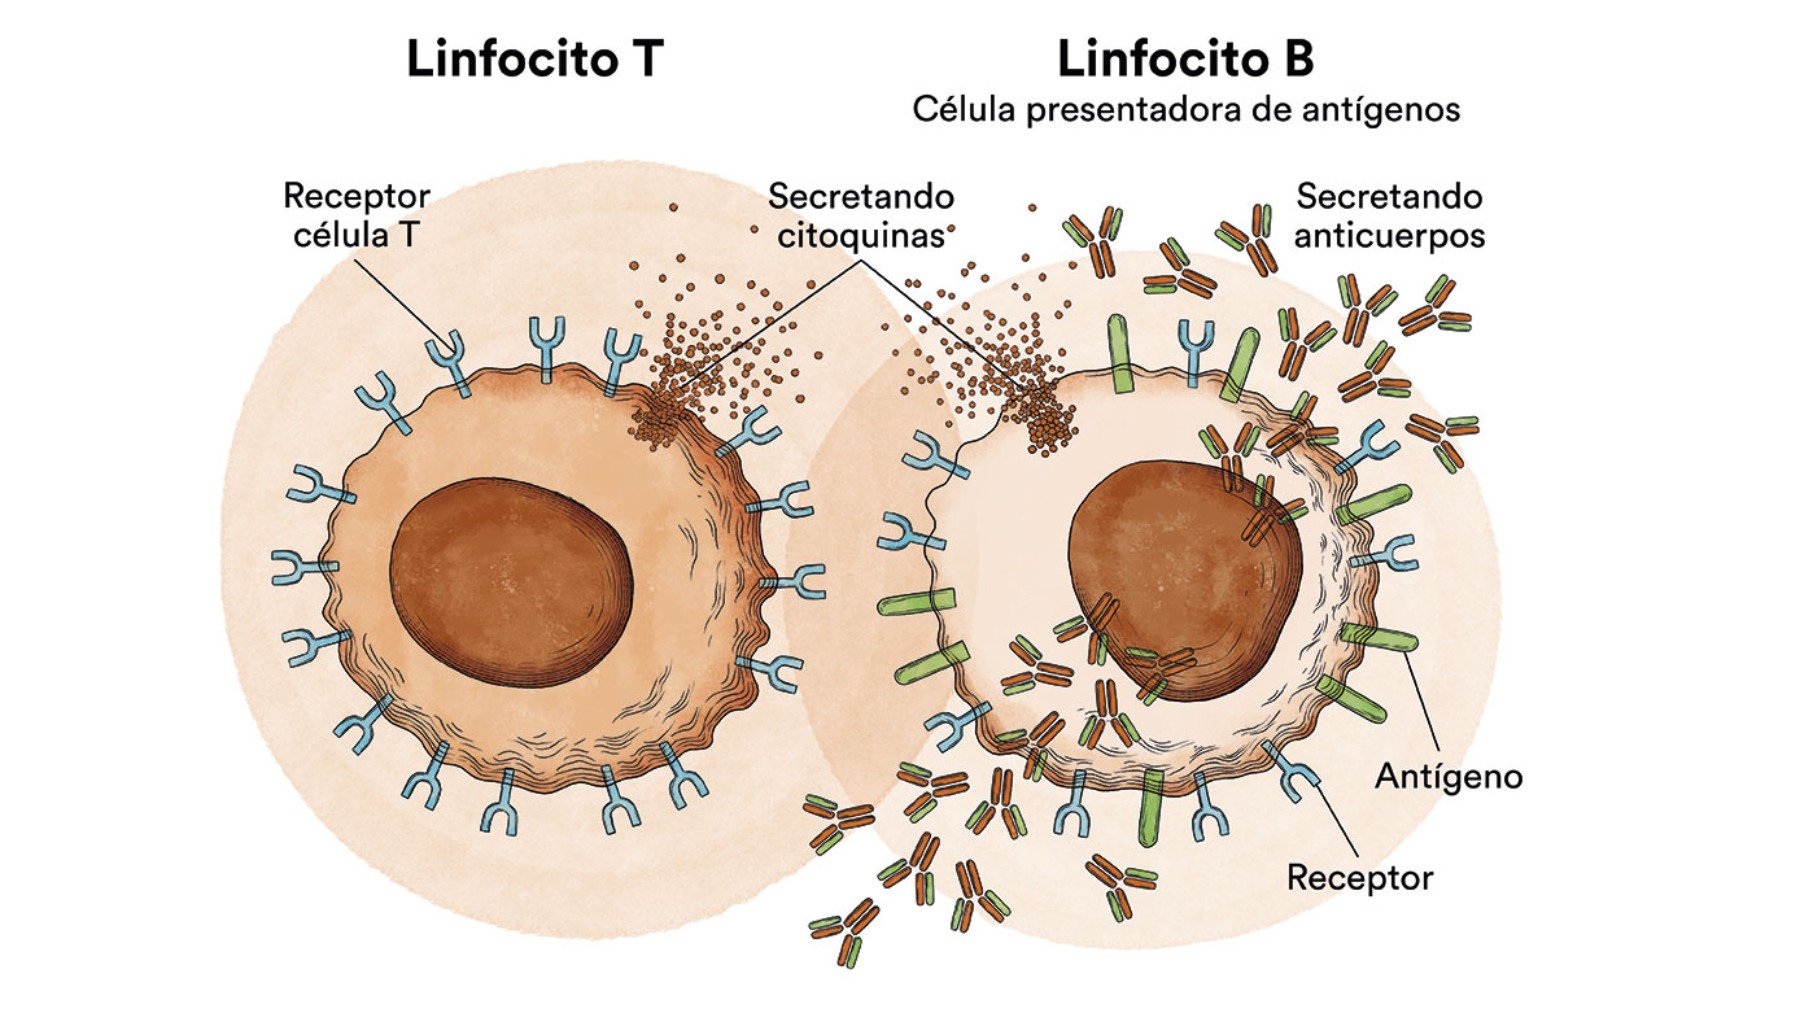

El Grupo de Inmunología Tumoral de la Universidad de Oviedo, perteneciente al Instituto Universitario de Oncología del Principado de Asturias (IUOPA) y que también forma parte del Instituto de...